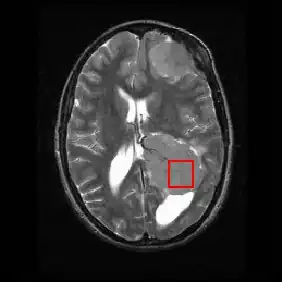

Neuroimaging contains a variety of techniques to directly or indirectly image of the structure, function/pharmacology of thenervous system. It is a relatively new fields within medicine, neuroscience and psychology.[22] Physicians who specialize in the performance and interpretation of neuroimaging in the clinical setting are neuroradiologists.

Neuroimaging is classified into two categories:

- Structural imaging, which deals with the structure of the nervous system and the diagnosis of gross (large scale) intracranial disease (such as tumor), and injury.

- functional imaging for diagnosing metabolic diseases and lesions on a finer scale (such as Alzheimer's disease) and for neurological and cognitive psychology research and building brain-computer interfaces.

| Imaging Modality | Technique | Advantage | Comparison | Image |

|---|---|---|---|---|

| General radiography | Passes electromagnetic radiation(x-rays) through body which either is absorbed by dense objects(eg.bones) or passes through to a detector on the other side of the body, creating an image | Rapid, cheap, nonvasive | minor radiation exposure | |

| CT | Passes x-rays through the body while the detector and x-ray generator rotate around the body, generating various images/slices of the body in each plane | Rapid,noninvasive | Radiation Exposure | |

| fMRI | Tracks blood flow and oxygen levels which proper neuronal activity;often superimposed on structural MRI slices for orientation; can be linked in time with MMG | Noninvasive, no radiation injection, or ingestion required | Blood flow/oxygen depend on the cardiovascular level response; results in temporal delay between stimulus and output | |

| MRI | Uses magnetic field and radio waves to create images of variably aliened and misaliened hydrogen ion in the tissue | Noninvasive, precise, no radiation | Expensive, no permission in patients with metal biomedical implants or clips/stents or severe clastrophobia |

|

| DTI | Tracks water movement along neural pathways as proxy for neural activity;simultaneously | Noninvasive, no radiation, injections, or injestions required. | Interpretation can be complex |

| PET/SPECT | Uses radio isotope(ingested or injected; measures uptake of the radioisotope; allows in vivo monitoring of molecular changes; used with structural imaging | Molecular changes visible in real time | Radioactive substance, minor radiation exposure |